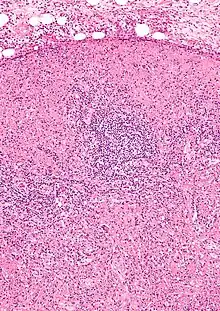

| Micrograph of a lymph node with Kikuchi disease showing the characteristic features (abundant histiocytes, necrosis without neutrophils). H&E stain. | |